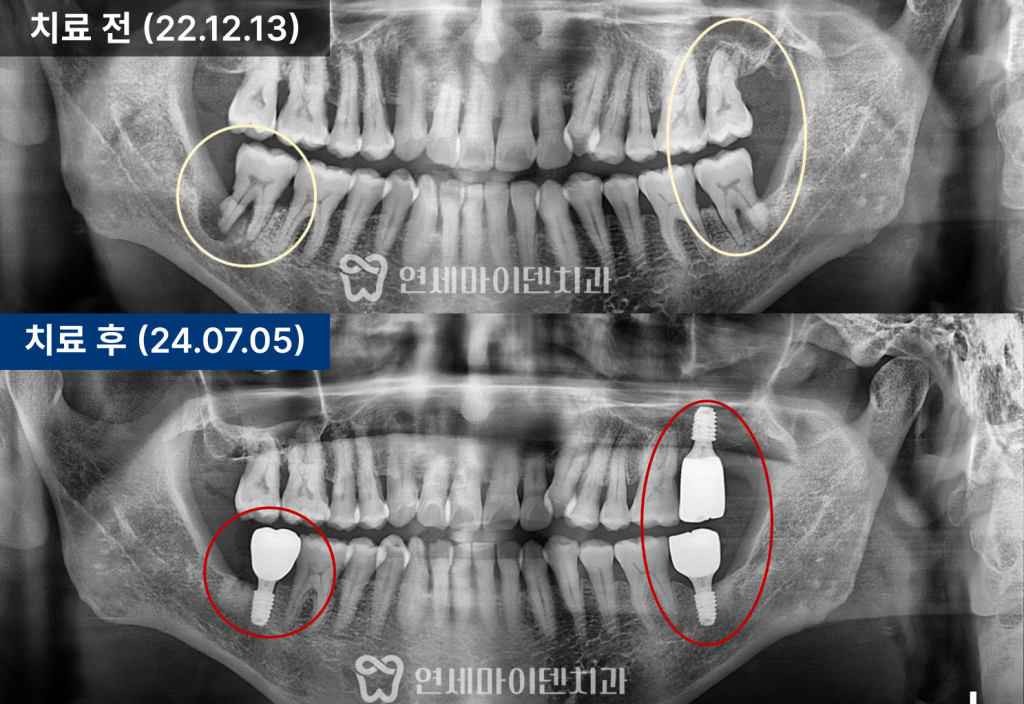

어금니 임플란트 증례: 치주질환 치료

이번 사례는 심한 치주염으로 인해

세 부위의 임플란트 치료를 시행한 환자 사례입니다.

엑스레이 검사 결과, 해당 치아의 뿌리 주변 치조골이

심하게 흡수된 상태로 확인되었습니다.

또한 반대편 어금니와 상악 어금니에서도

동일하게 치주염이 진행되어

총 세 부위에 대한 치료가 필요하다고 판단하였습니다.